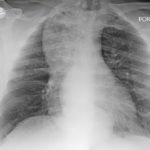

The chest X-ray demonstrated a markedly widened mediastinum (red brackets), raising concern for thoracic aortic aneurysm/aortic dissection, which prompted labs and contrast-enhanced computed tomography (CT) of the chest. The CT revealed a dilated proximal esophagus that narrowed distally (yellow tracing and red arrow), with particulate material, mass-effect on the trachea (purple outline), and bilateral patchy opacities suggesting aspiration. Barium esophagram showed a drastically dilated esophagus filled with contrast (yellow arrow), terminating into the classic “bird’s beak sign” (red arrow) at the lower esophageal sphincter (LES). Esophageal manometry later confirmed achalasia, proving that widened mediastina can have unexpected etiologies.